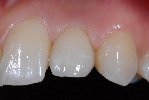

- Komplette Regeneration der Pappille 3 Monate nach der Eingliederung der Implantatkrone

- Vollkeramische Restauration auf Implantat